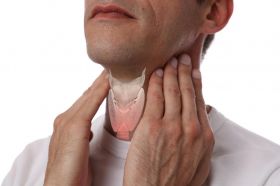

Hormones & Immunoassay test